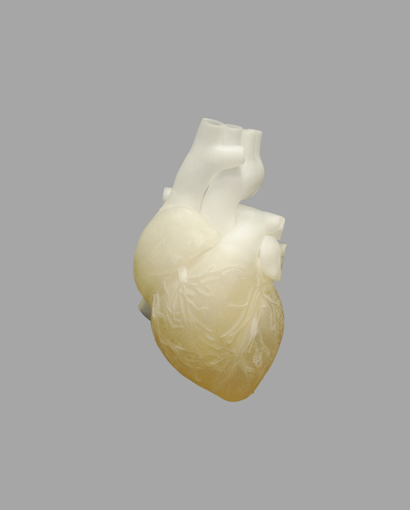

VisiJet M3 Pearlstone (MJP)

VisiJet M3 Pearlstone is a rigid plastic material with a stone-like finish, ideal for producing highly accurate dental models. It enables cost-effective manufacturing of crowns, bridges, orthodontic devices, and implants with excellent detail and dimensional accuracy.